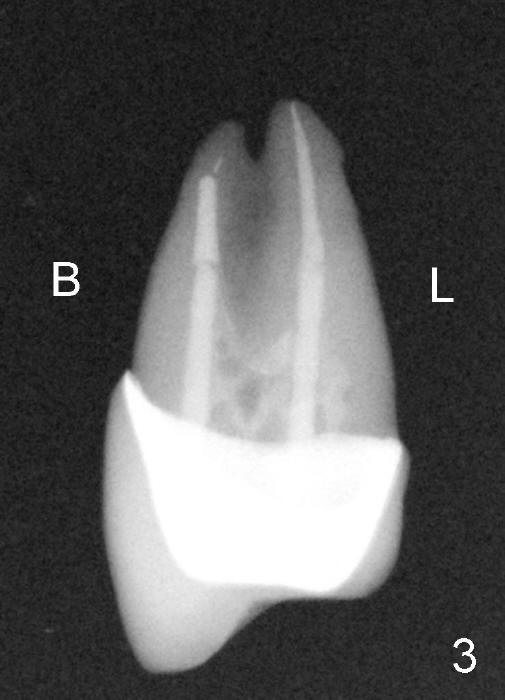

A 50-year-old man has mild pain in the upper left 1st bicuspid 3 years after root canal retreatment with placement of two posts (Fig.1). Findings of clinical exam are consistent with root fracture (Fig.2). Extraction reveals two fused roots (Fig.3,4). Probing indicates that the buccal plate is defective. Osteotomy is initiated in the palatal socket with a 2 mm pilot drill, followed by 2.5 and 3.0 mm reamers and 4.5x20 mm tap. The septum appears to have been pushed buccally (Fig.5 *) and form a new buccal wall (partially, strengthened by bone graft mentioned below) for the implant to be placed. The implant (4.5x20 mm) is placed in the palatal socket (Fig.6 *) with insertion of an abutment (A: 3.5x5 mm 0º), while a mixture of autogenous bone (harvested from reamers) and Synthograft (Bicon) is placed in the shrunken buccal socket (Fig.7; using allograft may decrease postop bony shrinkage). The bone graft is then contained by an immediate provisonal without collagen membrane or flaps. The patient is doing well postop. The gingiva is healthy (Fig.8*) when the provisional is removed 3 months postop with normal papillae (Fig.9 arrowheads). It remains the same 1 month post cementation (Fig.10,11). For further follow up, see immediate implant of the tooth #13.